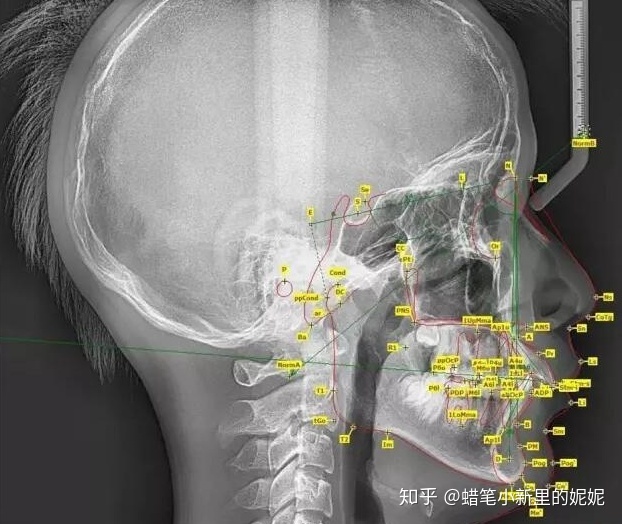

为了帮助医师准确的分析患者的具体情况,医师需要帮准备矫正的患者拍摄全景牙片以及头颅侧位片。

效果:通过全景片我们可以看到牙齿的数目是否有异常情况(例如:主要是颌骨内有无多生牙,埋伏牙等),牙根的情况(如:包括形态,位置,牙根有无吸收等),牙槽骨的 情况,牙周组织的健康状况,髁状突的状态等。

头颅侧位片的参考价值与全景片一样重要,在头颅侧位片上我们可以直接测量上下颌骨畸形的程度,分析引起错合畸形的原因是颌骨的问题还是单纯的牙齿问题,测内容 包括硬组织和软组织的测量,这些数据是拟定医治计划的重要信息,在医治计划的确定上起到了举足轻重的效果。